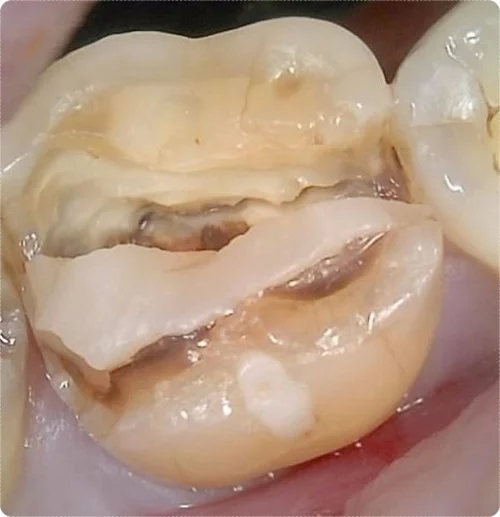

두 번째 환자분은 같은 날 내원하셨지만, 치아 손상이 훨씬 심했습니다.

치아에 명확한 파절과 균열이 있었고, 환자분 스스로도 심한 통증을 느껴 내원하셨습니다.

손상이 너무 심하여 자연치 보존이 어렵다고 판단했고, 발치 후 임플란트를 진행하게 되었습니다.